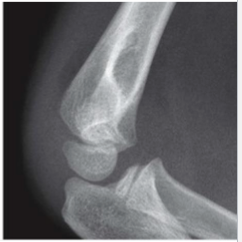

What is this

normal elbow

post + ant fat pad